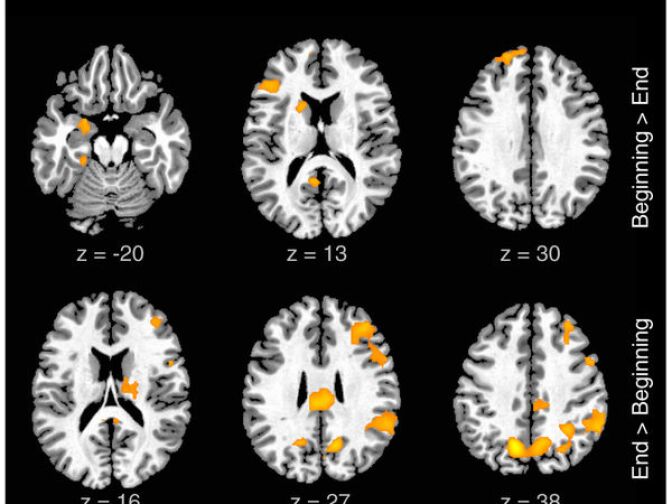

In both conditions, Braun explained, “we acquired images related to brain activity, and this is using an fMRI method,” (functional MRI) “and that tells us what areas of the brain are more or less active and we can get a picture of what the brain is doing, specifically during freestyle rapping.”

Braun examined the brain images of the rappers while they were freestyling rhymes. He found an interesting pattern of activity in the prefrontal cortex. Basically, the areas associated with self-generated and self-motivated behavior were active but the areas that monitor or censor behavior were de-activated. So while there is an aspect of the brain that is energized by using improvisational skills, there is much less self-censoring at play.